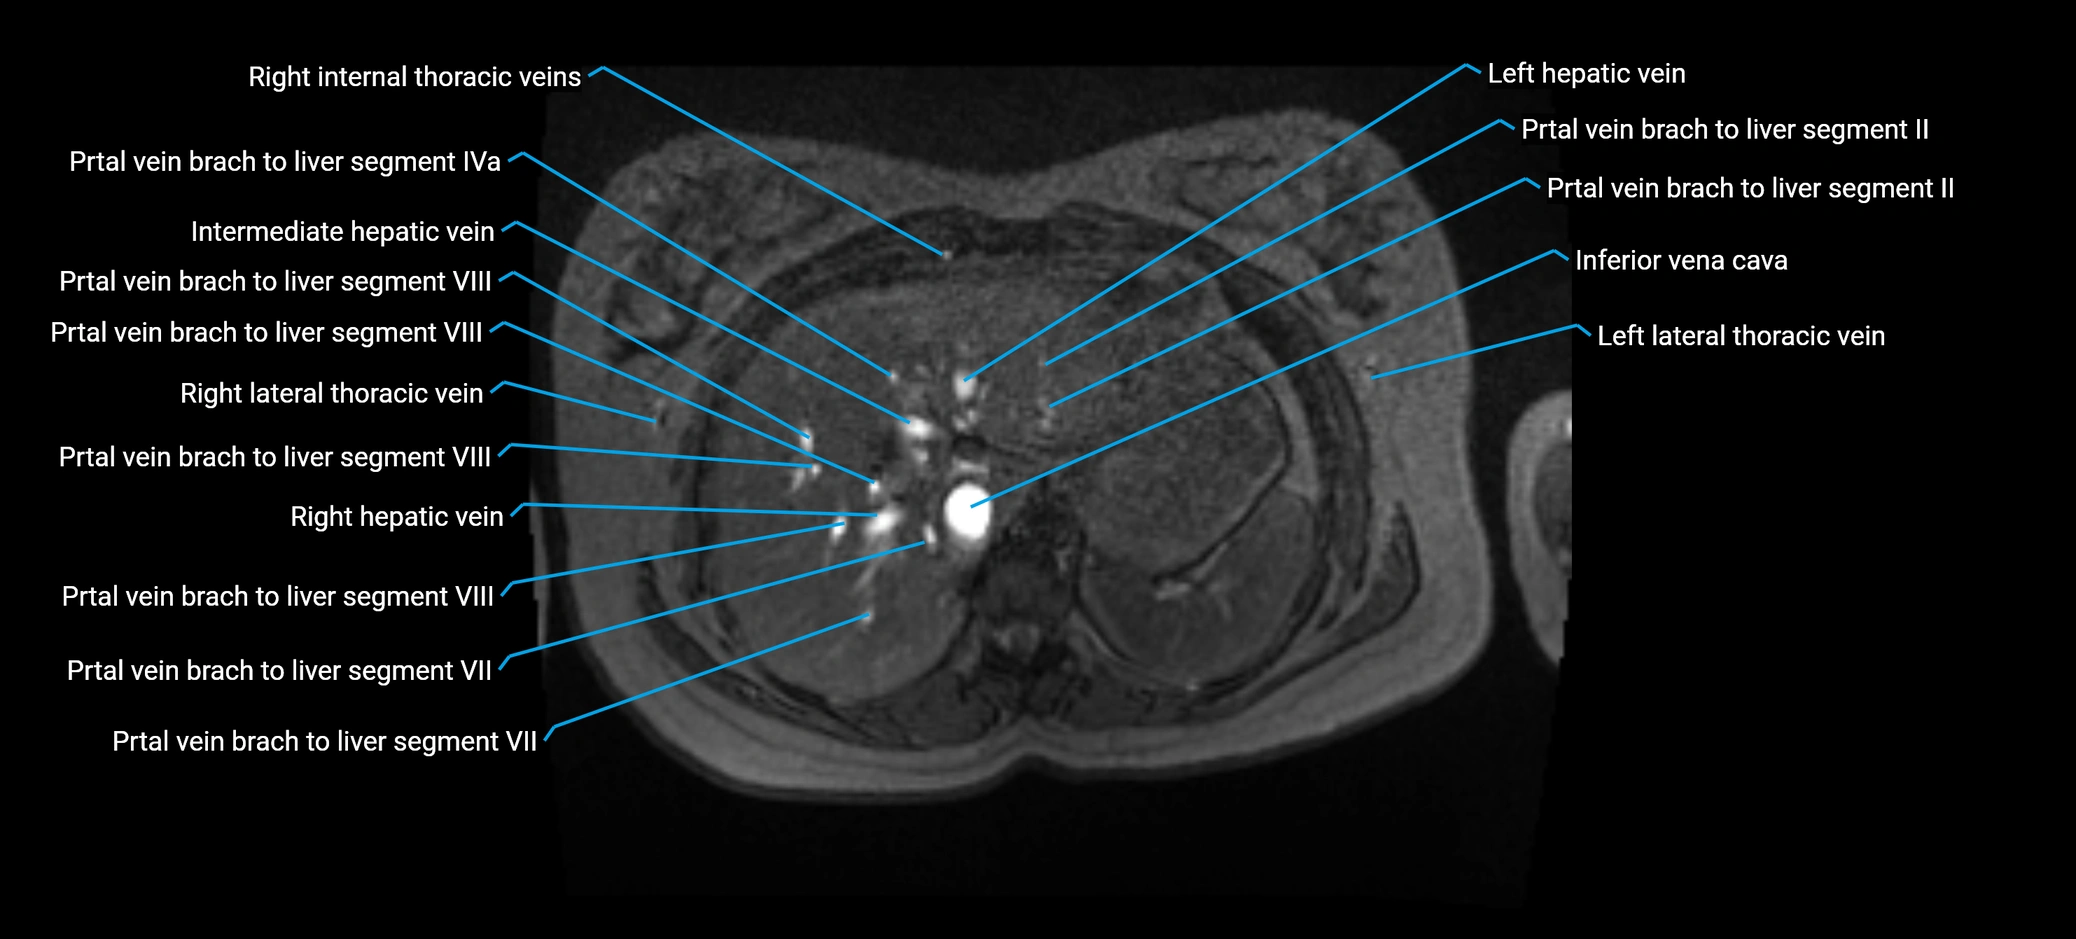

MRI image

image